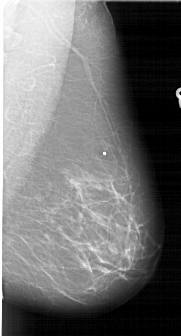

A_1687_1.LEFT_MLO

LEFT_MLO LINES 6451 PIXELS_PER_LINE 3796 BITS_PER_PIXEL 12 RESOLUTION 43.5 OVERLAY

FILE: A_1687_1.LEFT_MLO.OVERLAY

TOTAL_ABNORMALITIES 1

ABNORMALITY 1

LESION_TYPE MASS SHAPE LOBULATED MARGINS ILL_DEFINED

ASSESSMENT 4

SUBTLETY 4

PATHOLOGY BENIGN

TOTAL_OUTLINES 1

BOUNDARY